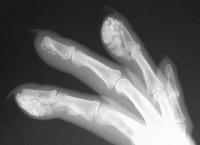

The right index and middle fingertips are large, hard and tender.

Xrays show extensive soft tissue calcifications of the distal pulp of these fingers.